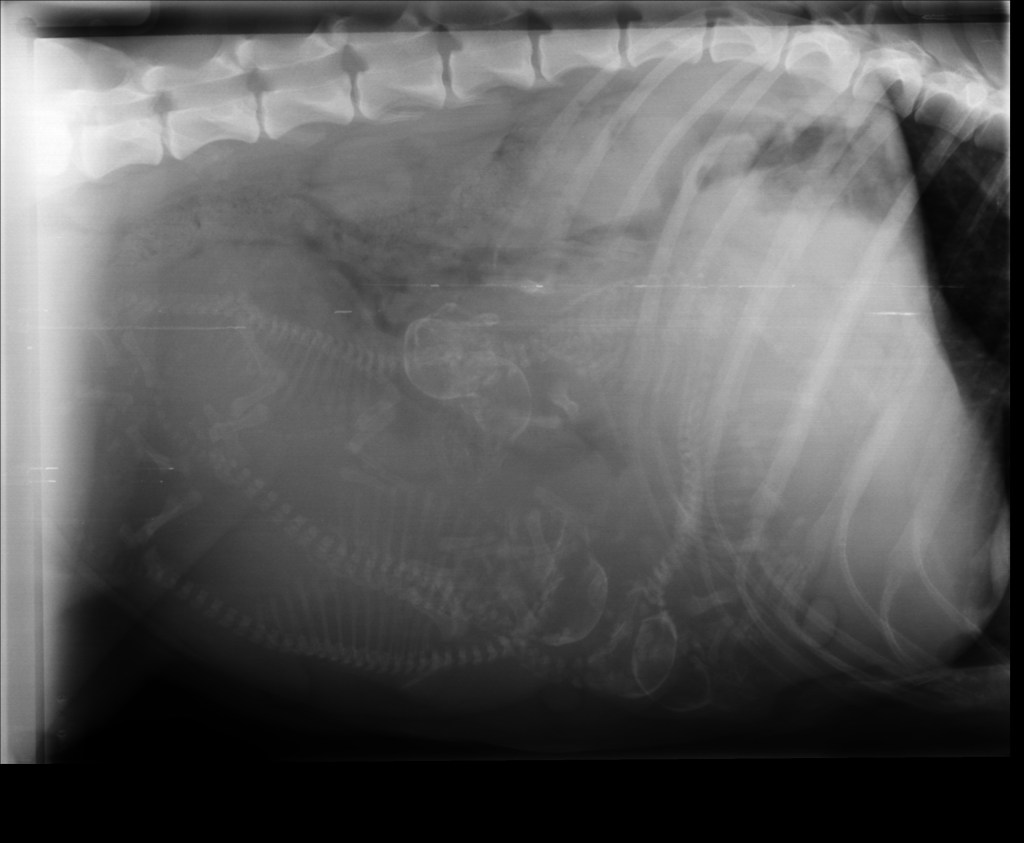

Hvor mange ser du?

Hei! Da har vi vært inne til røntgen av magen til Izel. Hvor mange teller du? Vi så hvertfall 5 hos veterinær. Legger ved både redigert bilde så det skal være enklere å telle i tillegg til original. Trykk på bildene for å se det i større format.